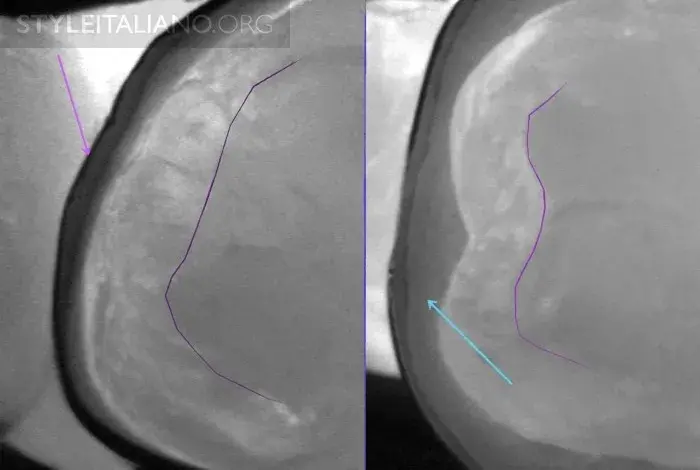

Рис. 15 — Предоперационный вид/ Лазерное просвечивание/ Рентген.

Рис. 16 – Просвечивание зубов показывает полости в истинном размере, а на рентгене они уменьшены.

Рис. 17 – Рентген слева, просвечивание справа.